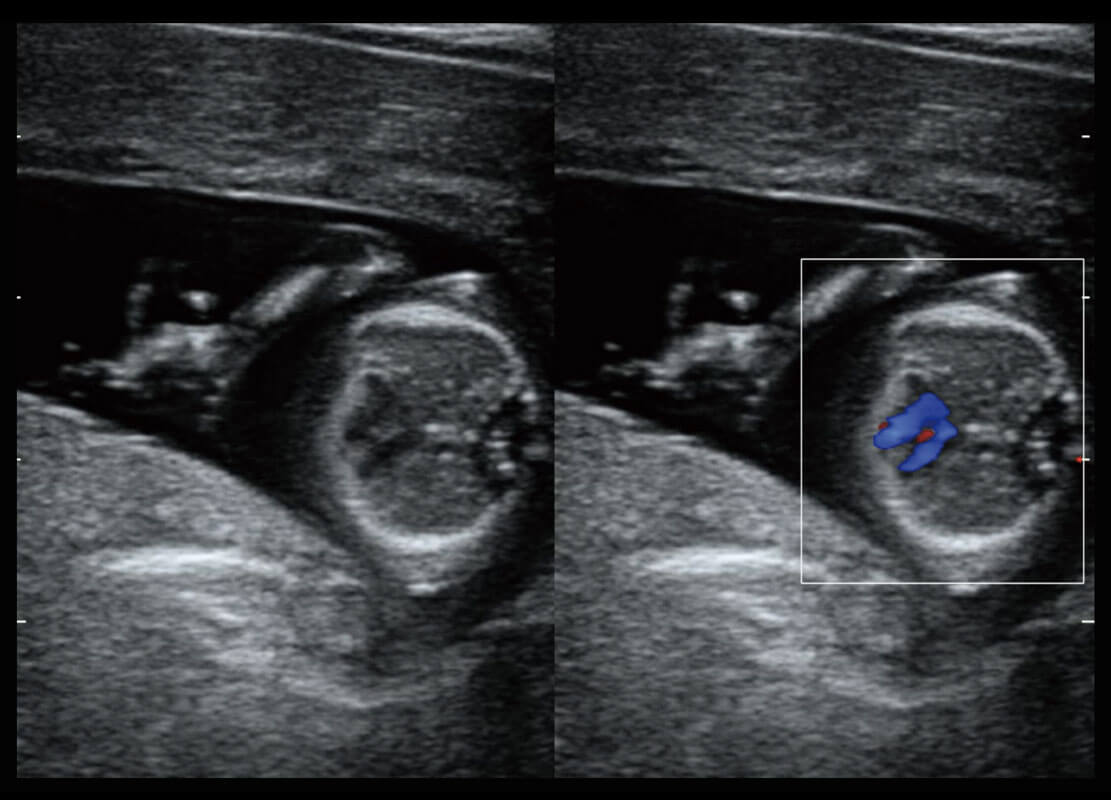

P60搭載寬頻帶線陣探頭、寬景成像、彈性成像技術(shù),為您提供乳腺應(yīng)用方案。P60支持高頻相控陣探頭、線陣探頭、腹部高頻探頭、腹部微凸探頭等,豐富的探頭群搭載敏感的彩色血流成像,適用于新生兒多種臟器檢測要求,滿足新生兒篩查需求。

新生兒肝血管癌

新生兒脊髓圓錐

新生兒心臟